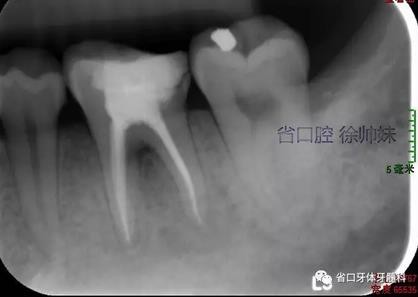

根尖片(圖4)示36根尖周低密度影明顯較前消退,根分叉仍有少許低密度影。

圖4 術(shù)后4月